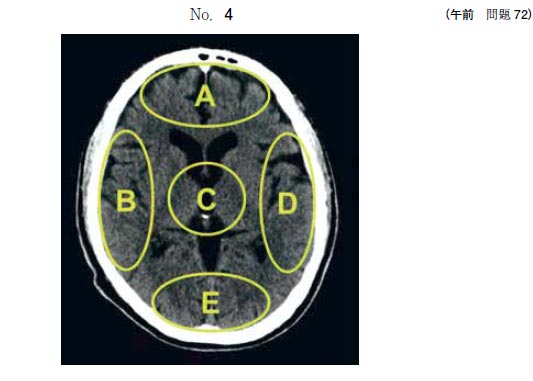

72 頭部CT(別冊No.4)を別に示す。

論理的思考を制御する領域はどれか。

図

•  1.A

•  2.B

•  3.C

•  4.D

•  5.E